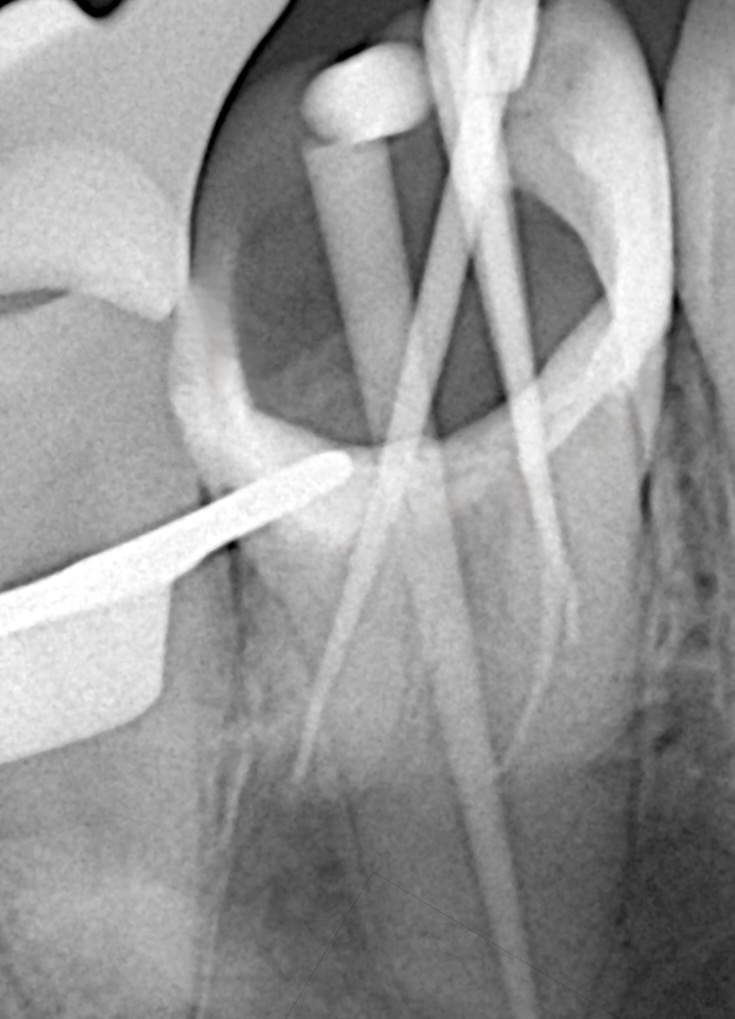

1. ENDODONTIC DIAGNOSIS & CLEANING UNDER MAGNIFICATION

Microscope-Guided Access

Scopes improve canal identification, help remove overhanging dentin, and ensure minimal tooth removal.

The canals were shaped using a hybrid rotary-reciprocation sequence, respecting original canal anatomy.

Irrigation Protocol

- Sodium hypochlorite (5.25%) activated ultrasonically

- EDTA 17% for smear layer removal

- Chlorhexidine 2% for final disinfection

Activation improves penetration and reduces bacterial load significantly.

Bioceramic Obturation

The canals were obturated with a bioceramic sealer due to:

- Superior sealing ability

- Alkaline pH promoting periapical healing

- Hydrophilic bonding to dentinal walls

- Zero shrinkage and bioactivity

This helps reinforce the endodontically treated tooth internally.